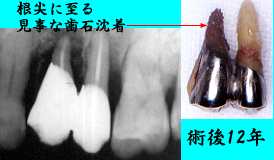

| 初診時 パノラマ | 術後12年 Dentalおよび抜去歯牙 |

| |45Fop+HAP 49歳 男性 |

排膿・咬合痛が著明となる |

初診時口腔内およびX線所見:

やや褐色がかった色と、咬耗状態からして一見丈夫そうな歯ではあったが、清掃状態が悪く

歯肉縁下歯石の沈着も著明。歯槽骨吸収程度も中程度〜重度でほぼ年齢相応で、まさに

処置および経過:

動揺の著しい|45を抜髄のうえ、歯周外科手術(Fop)および人工骨移植(HAP)を

行い、補綴物による連結固定を行った。なお、固定はやや不十分ではあったが、周囲の歯

への影響を考慮して2歯のみの連結とした。

他の部位に対しても歯周外科処置を伴う一連の歯周治療を行ったのち、メインテナンスに移行。

仕事の関係上、定期的なメインテナンスが不可能で、2〜3年に数度の追加処置および歯石の

除去を行いながら12年経過。1年程前より同部の腫脹や違和感を訴えるも、消炎処置にて症状の

緩和を試みる程度で経過観察。今回いよいよあきらめがついたという感じの来院であった。

考察:

歯周外科処置により一度は完全に除去された歯石ですが、12年の歳月とメインテナンスの間隔

が災いして少し早めの抜歯となったような気がします。一度除去して、根面を研磨したとはいえ、

うかうかすると簡単に再付着する歯石の恐ろしさを再認識した症例です。

感想:

根尖部に至る見事な歯石沈着に思わず感激した反面、|5の比較的綺麗な状態に

抜歯を早まったと反省。